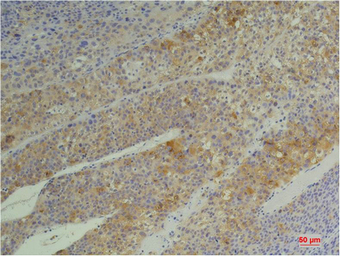

IHC-P analysis of human pancreatic carcinoma tissue using GTX34136 Cyclophilin B antibody [1B3].

Dilution : 1:200